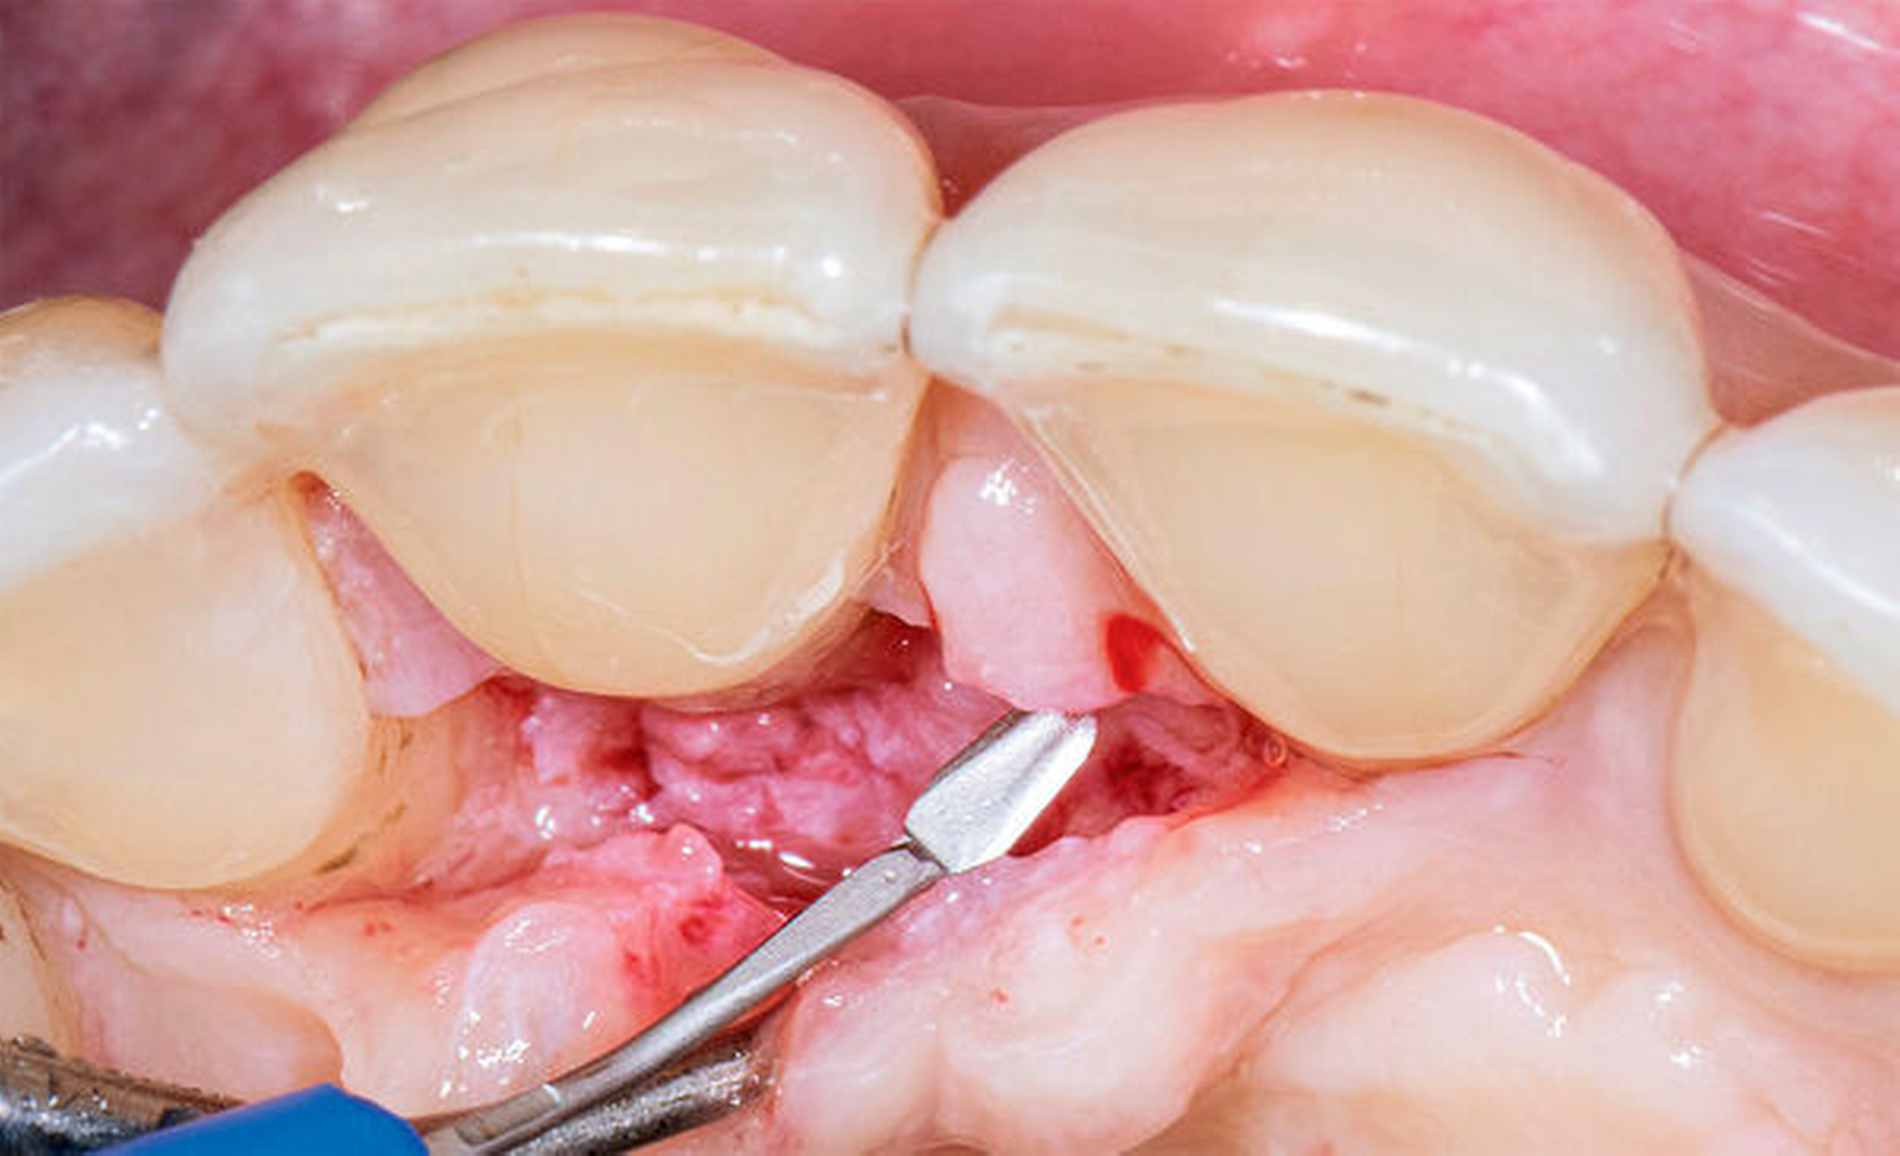

Neue Trends und Entwicklungen in der modernen Oralchirurgie gehen allerdings in Richtung sehr feiner Skalpellklingen, die extrem kleine chirurgische Zugänge ermöglichen und noch weniger invasive mikrochirurgische Techniken erlauben [Rebele et al., 2014; Zuhr et al., 2018]. Auf dieser Grundlage lässt sich vermuten, dass die mikrochirurgischen Instrumente und Nahtmaterialien in der oralen Mikrochirurgie in Zukunft wieder kleiner werden könnten und deshalb auch wieder höhere Vergrößerungsfaktoren für die zu ihrer Anwendung erforderlichen Sehhilfen notwendig werden (Abbildungen 5 bis 16). So wie es in anderen mikrochirurgischen Fachdisziplinen bereits heute Realität ist, könnten vor diesem Hintergrund auch zukünftige Generationen dentaler Operationsmikroskope im Hinblick auf Flexibilität, Workflow und Anwenderfreundlichkeit verbessert und auf diese Weise wieder einen festen Platz in einer oralchirurgisch tätigen Praxis einnehmen. Eine gute Perspektive könnten auch innovative Lupensysteme darstellen, die bereits heute mit Vergrößerungsfaktoren von 9.0x bis 10.0x angefertigt werden können.

Ein in diesem Sinne präzises, atraumatisches und minimalinvasives operatives Vorgehen wird ohne Zweifel durch die Anwendung stark vergrößernder Sehhilfen oder dentaler Operations-mikroskope beziehungsweise auch damit einhergehend durch die Verwendung mikrochirurgischer Instrumente und Nahtmaterialien deutlich erleichtert. Ein mikrochirurgischer Ansatz fand erstmals in den frühen 1990er-Jahren in der rekonstruktiven Parodontal- und Implantatchirurgie Erwähnung [Bittencourt et al., 2012; Shanelec & Tibbetts, 1992].